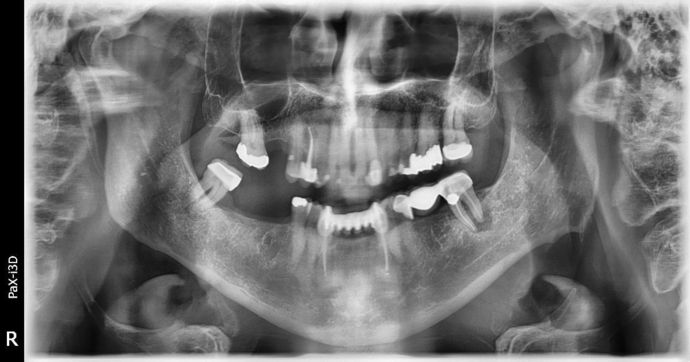

Dental Implants: Case 2 - Sweeny

Another Great case we finished up! Patient had lost a bridge on lower left side due to a cracked root and large decay on the other anchor tooth. Bridge was sectioned and teeth were removed. On the right side, wisdom tooth was hyper-erupted and had poor prognosis due to bone loss. Wisdom tooth was removed. Left side had bone graft placed and three months later 3 implants were placed. Right side had 2 implants placed at the same time. After healing, Implants were restored with bridge on left side and separate crowns on right side. The model is of the patient before surgery (no photos were available), actual photo is of patient after restorations finished. LOVE THE OUTCOME!